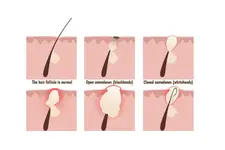

Kuyruk sokumu kıl dönmesi, tıbbi literatürde "pilonidal hastalık" olarak bilinen bir durumdur. Bu hastalık, kuyruk sokumu bölgesinde kılların derinin altına doğru büyüyerek iltihaplanmasına ve enfeksiyon oluşturmasına yol açar. Genellikle genç erkeklerde daha sık görülmekle birlikte, kadınlarda da ortaya çıkabilir. Bu makalede, kuyruk sokumu kıl dönmesinin belirtileri, nedenleri ve tedavi yöntemleri üzerinde durulacaktır. Belirtiler Kuyruk sokumu kıl dönmesinin belirtileri genellikle şu şekildedir:

Bu belirtiler, hastalığın evresine göre değişkenlik gösterebilir. Başlangıçta hafif rahatsızlık hissedilse de zamanla belirtiler şiddetlenecek ve yaşam kalitesini olumsuz etkileyecektir. Nedenleri Kuyruk sokumu kıl dönmesinin kesin nedeni henüz tam olarak anlaşılamamıştır. Ancak, bazı faktörlerin hastalığın gelişiminde etkili olduğu düşünülmektedir: